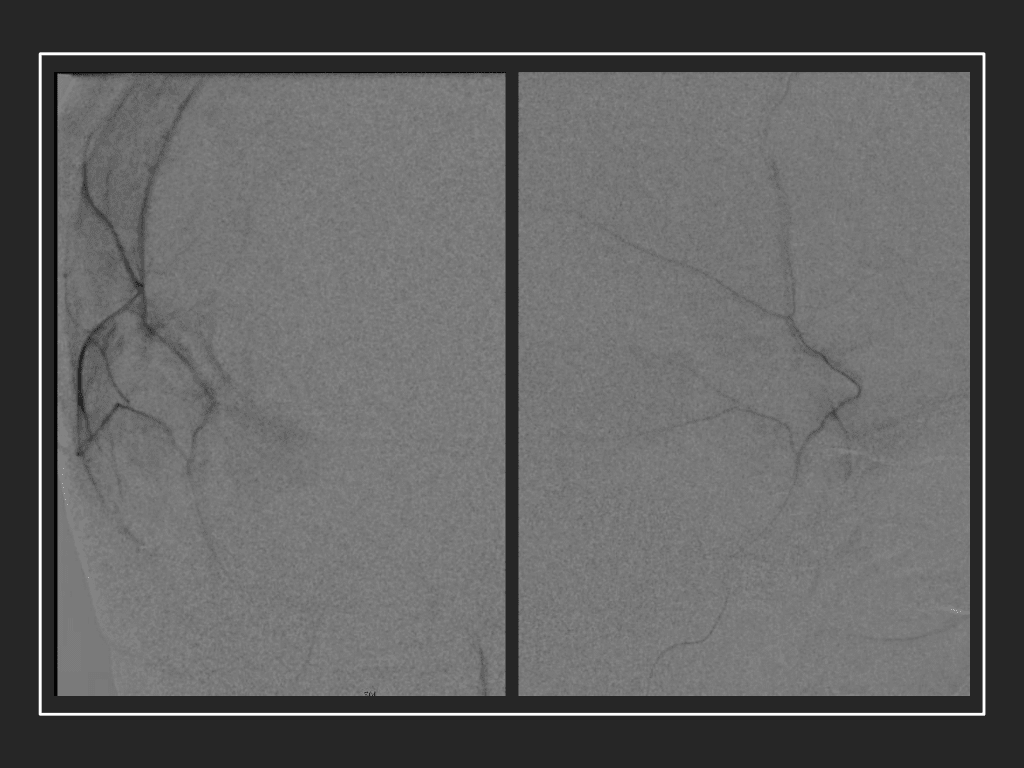

The patient agreed to receive minimally invasive treatment with Bilateral Middle Meningeal Artery Embolization, a new approach to promote resorption of chronic and subacute subdural hematomas in patients that are not improving with conservative measures or have contra-indications to surgical evacuation. Selective catheterization of the Middle Meningeal Artery is followed by transarterial embolization of the territory and inflammatory membranes that are felt to be secreting serosanguinous proteinaceous exceeding the capacity for resorption. MMA embolization was performed bilaterally in this patient. (Figure 2. A and B)

Figure 2. A) Initial right ECA angiogram ; B) Post MMA Embolization; C) Selective Embolization Of Middle Meningeal Artery Membranes using PVA particles (arrows).